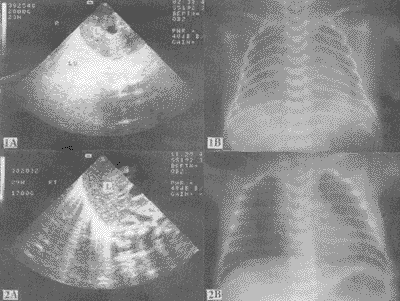

22例有严重的呼吸系统症状的早产儿中, 17例超声所见在肝(脾)后有弥漫的高强回声(图1)。 X线胸片呈典型的“白肺”。 根据临床表现及X线检查确诊为严重的HMD。 9例于生后2天内死亡。 经家属同意的7例尸检证实为肺透明膜病。 1例孕28周早产儿, 死前B超检查发现肝(脾)后强回声, 在死后半小时B超检查时, 强回声消失。 超声发现3例肝(脾)后呈稀疏的放射状强回声, X线胸片报告HMD早期(图2)。 2例超声检查在肝(脾)后未见任何回声, X线胸片也未提示肺部异常。 对9例存活的肝(脾)后有强回声的早产儿进行超声随访, 其强回声在3天内消失的5例, 7天内消失的3例。 仅1例于生后41天强回声才消失。 以上早产儿中有不同程度的肺部其他疾患(如肺炎等)。

图1A 典型的HMD患儿的声像图显示肝后弥漫的高强回声(L: 肝脏);

1B 该患儿的X线胸片呈典型的“白肺”

图2A 轻型HMD患儿的声像图显示呈放射状的中高回声;

2B X线检查提示HMD早期

40例正常足月新生儿中, 34例超声检查在肝(脾)后无任何回声, 同一天的X线胸片也提示心肺无异常(图3)。 6例超声见肝(脾)后稀疏的放射状强回声, X线胸片报告为湿肺(图4)。 40例新生儿均无呼吸系统症状, 在生后3~7天相继出院。